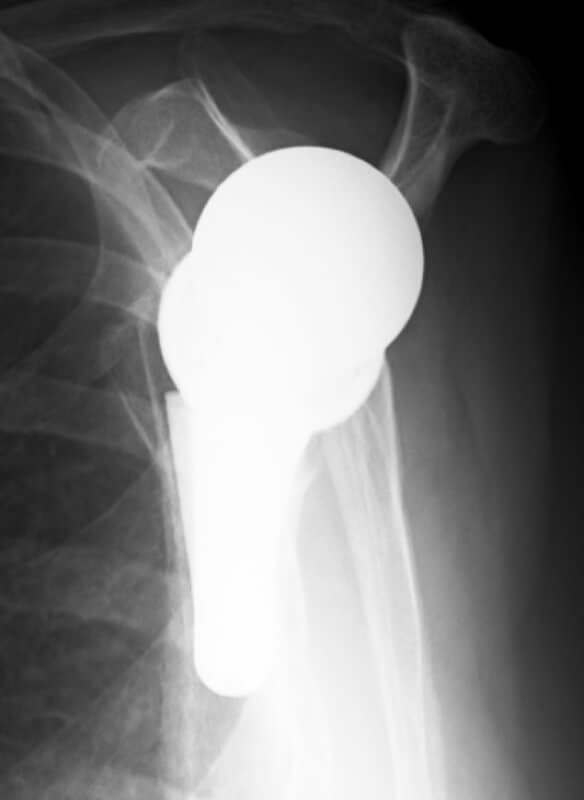

DePuy, Delta